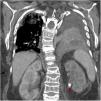

Mujer de 73 años trasladada desde el hospital comarcal con diagnóstico de shock séptico de origen urinario secundario a cólico renoureteral complicado (fig. 1, flecha roja) con absceso renal (fig. 2, flecha blanca) y neumonía abscesificada en base izquierda (fig. 2, flecha naranja) para control de foco. Comentado el caso con radiología vascular intervencionista, primero se realizó nefrostomía percutánea izquierda y posteriormente le colocaron drenaje en absceso de polo superior de riñón izquierdo aspirando contenido aéreo. Al infiltrar contraste, este evidenció la existencia de fístula renobronquial. En el abscesograma (fig. 3) puede objetivarse contraste en polo superior de riñón izquierdo (flecha blanca), lóbulo inferior de pulmón izquierdo (flecha naranja), árbol bronquial y bronquio principal izquierdo (flecha amarilla). Desde un primer momento la paciente recibió antibioterapia de amplio espectro con cultivos microbiológicos negativos.